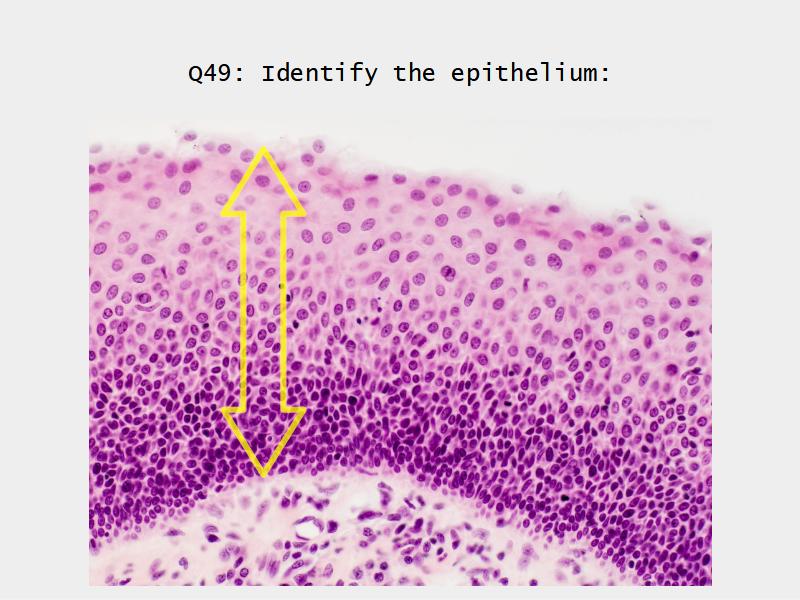

What cells are present?

Slides: Respiratory System

- Slide 71: Nostril

- Slide 72 & 74: Lung

- Slide 73: Trachea

- Slide 108: Olfactory epithelium

- Slide 111: Epiglottis